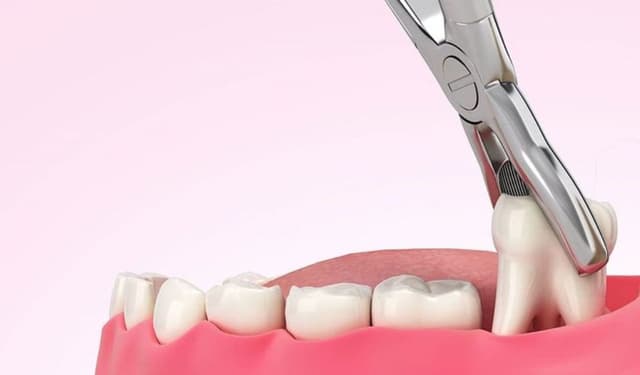

nhổ răng khôn

Trang chủ/nhổ răng khôn